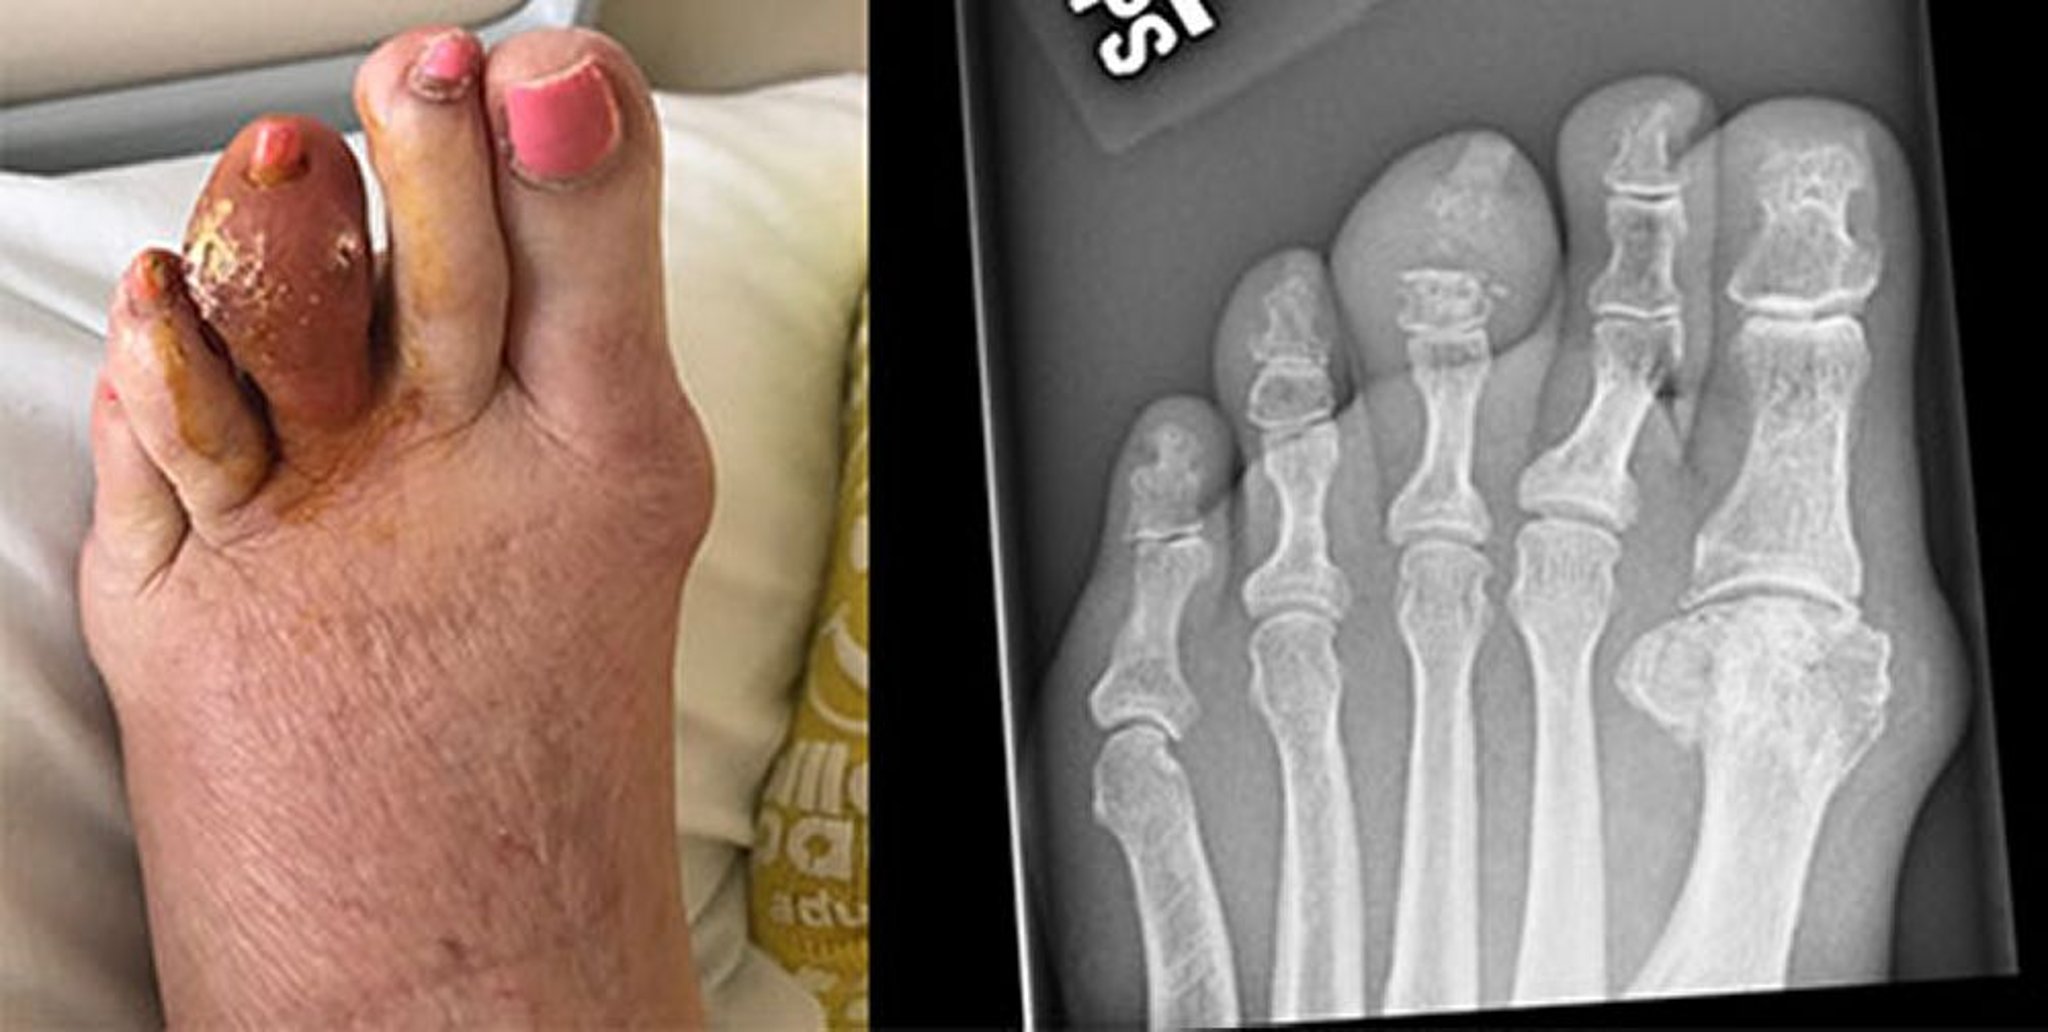

Bệnh gút của ngón chân giữa

Bức ảnh này cho thấy một sạn urat lớn của ngón chân thứ ba bên trái, phần này đã bị phá vỡ và giải phóng axit uric cứng. Phim chụp X-quang bên phải cho thấy tình trạng mòn xương đốt ngón giữa và khớp liên đốt ngón xa.

Hình ảnh do bác sĩ Brian F. Mandell cung cấp.